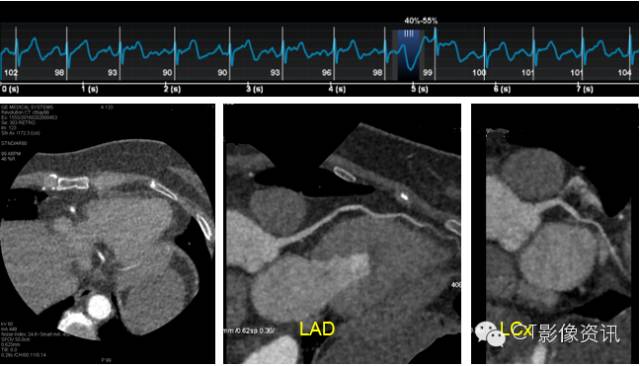

Case 3 男性,40岁,发作性心前区不适2天。

扫描协议 探测器宽度:120mm, Axial; 管电压和管电流:70kV, Smart mA; 旋转速度:0.28s/rot ;迭代:ASiR-V 50%;体重指数:22.16; 对比剂:270mgI/ml, 25ml, 4.2ml/s; 扫描剂量:0.162mSv。

CCTA所见 右冠状动脉起源变异,LAD近段非钙化斑块,管腔轻度狭窄。

点评 CT检查的安全包括X射线的辐射安全和对比剂的使用安全两个方面。人们希望在使用尽可能低的辐射剂量和低对比剂碘剂量的情况下获取临床能够接受的图像质量。这就是CT中的双低概念。

本例患者Auto-Gating技术自动推荐 ONEBEAT下 75%相位扫描,应用 Smart mA及 ASiR-V 技术实现了“双低”冠脉扫描,即低造影剂剂量和低射线剂量,且图像质量优秀,冠脉病变显示良好。本例有效剂量仅为0.162mSv。